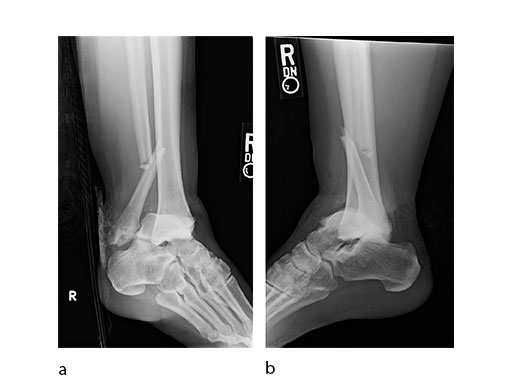

Case 3: Horse fall (Case provided by Mark Lee, Sacramento, USA)

A 45-year-old patient fell from his horse, receiving a closed bimalleolar fracture/ dislocation (Fig 10). Computed tomorgraphy demonstrated an additional anterolateral avulsion injury and syndesmosis dislocation. Osteosynthesis was conducted with a VA-LCP Lateral Distal Fibula Plate.

Push technique was required to achieve fibular reduction, and the syndesmosis was reduced and clamped with periarticular clamps (Fig 11). Postoperative x-rays at 4 weeks demonstrated good maintenance of reduction (Fig 12).